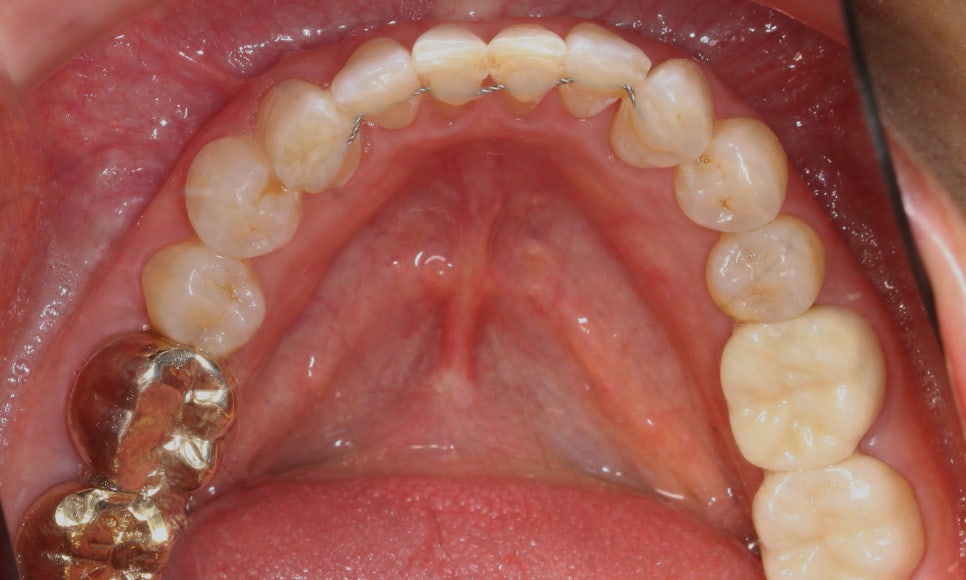

환자분의 아랫니 상태를 보시면

위처럼 앞쪽의 치아들이

심하게 삐뚤거리는 모습인데요,

치아 사이의공간이 좁아서

작은앞니(측절치)의 각도가

심하게 회전된 모습입니다ㅠㅠ

전체적인 아랫니의 치열도

심하게 삐뚤거렸던 처음 모습과 달리

아랫니 부분교정(2D교정)으로

이상적인 치아의 배열인 U-자 곡선의

형태로 바뀐 모습인데요!